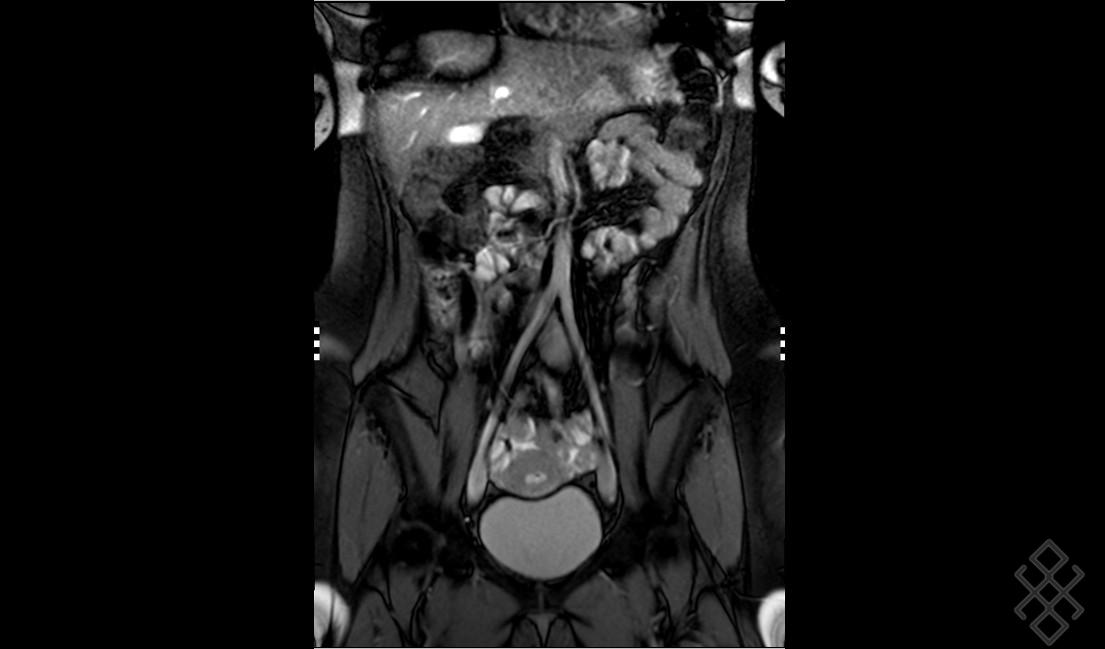

IRM de diffusion en pathologie pelvienne Figure 2. Ce lavement peu agréable n'est pas absolument indispensable, mais il est fortement recommandé car il permet une meilleure analyse des parois du rectum qui peut être atteint lors de l'endométriose. IRM pelvienne L'IRM est un examen non irradiant, sans risque, qui est très utile pour le diagnostic et le bilan d'une endométriose

IRM pelvienne Centre de radiologie Olympe Imagerie Antony. Pourquoi lavement rectal pour IRM pelvienne Didine - 3 nov du Microlax et éventuellement du produit de contraste gadoliné en fonction de l'indication de l'IRM pelvienne.